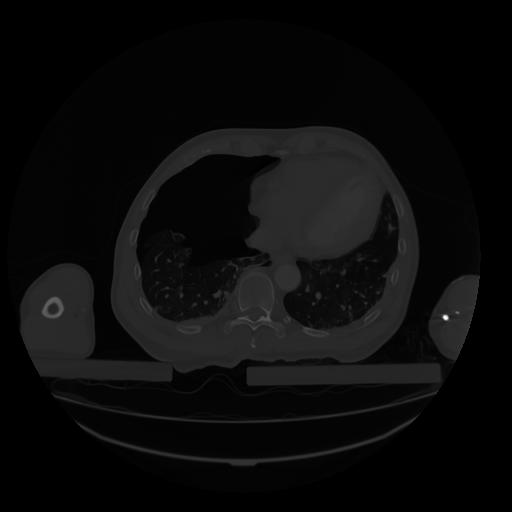

28 CUERPO,CE,Vol,2.0,CUERPO,,